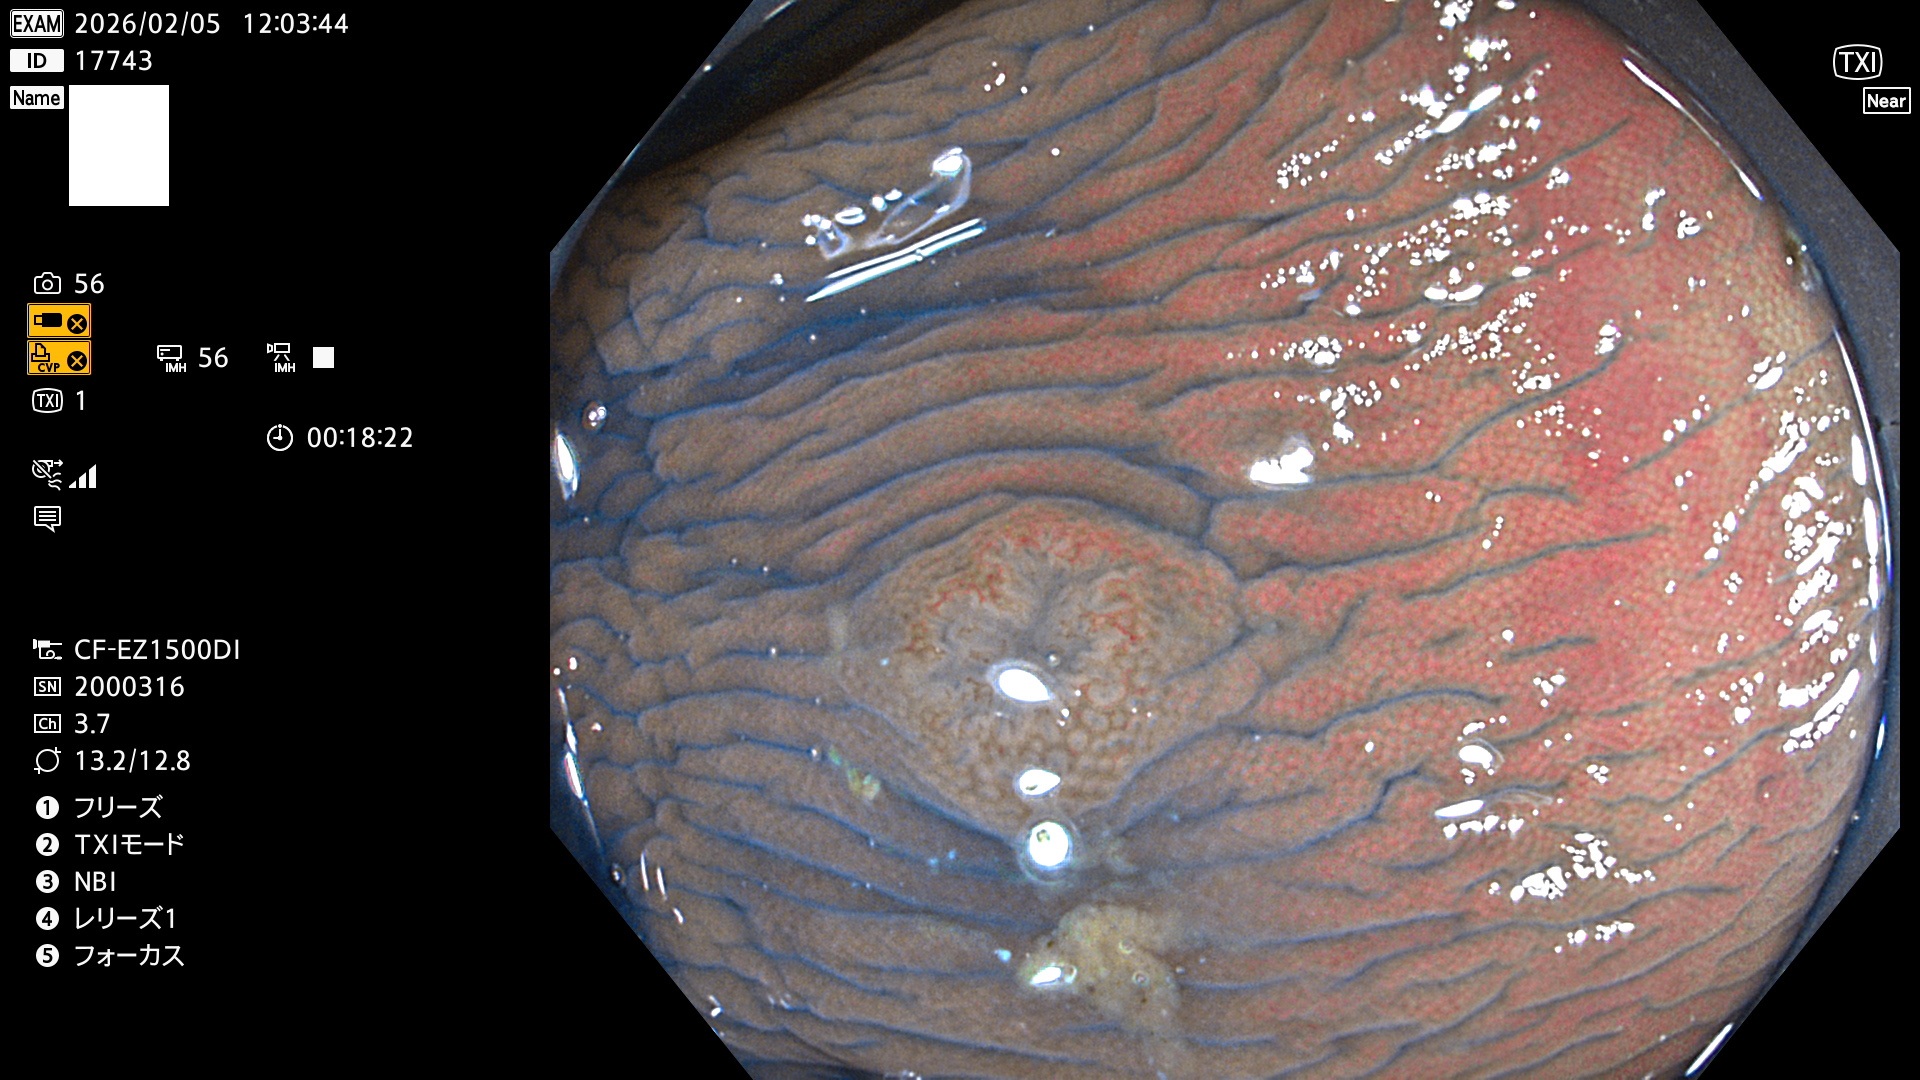

完全に平坦な物をUb、陥凹している物をUcと呼びます。Ubは認識が困難で、Ucはびらん(炎症)と紛らわしいために見落とされやすく、「内視鏡後・大腸癌」の原因になります。

専門的)Uc=De Novo癌? 内視鏡の解像度が低かった時代、このような説もありました。しかし今日の高精度内視鏡では良性の微小なUc型腺腫(APC遺伝子異常の腺腫)が日常的に見つかります。Ucこそが多段階発癌(Adenoma-Carcinoma Sequence)のMain Routeです。

毎週の検査(木・金・土・日)に発見されたUbとUc型・腺腫を、その週の日曜の夜にUPし1週間、提示します。

2026年2月5日〜2月8日の4日間(40件)9個 (Uc_ADR=9個/40人=23%)